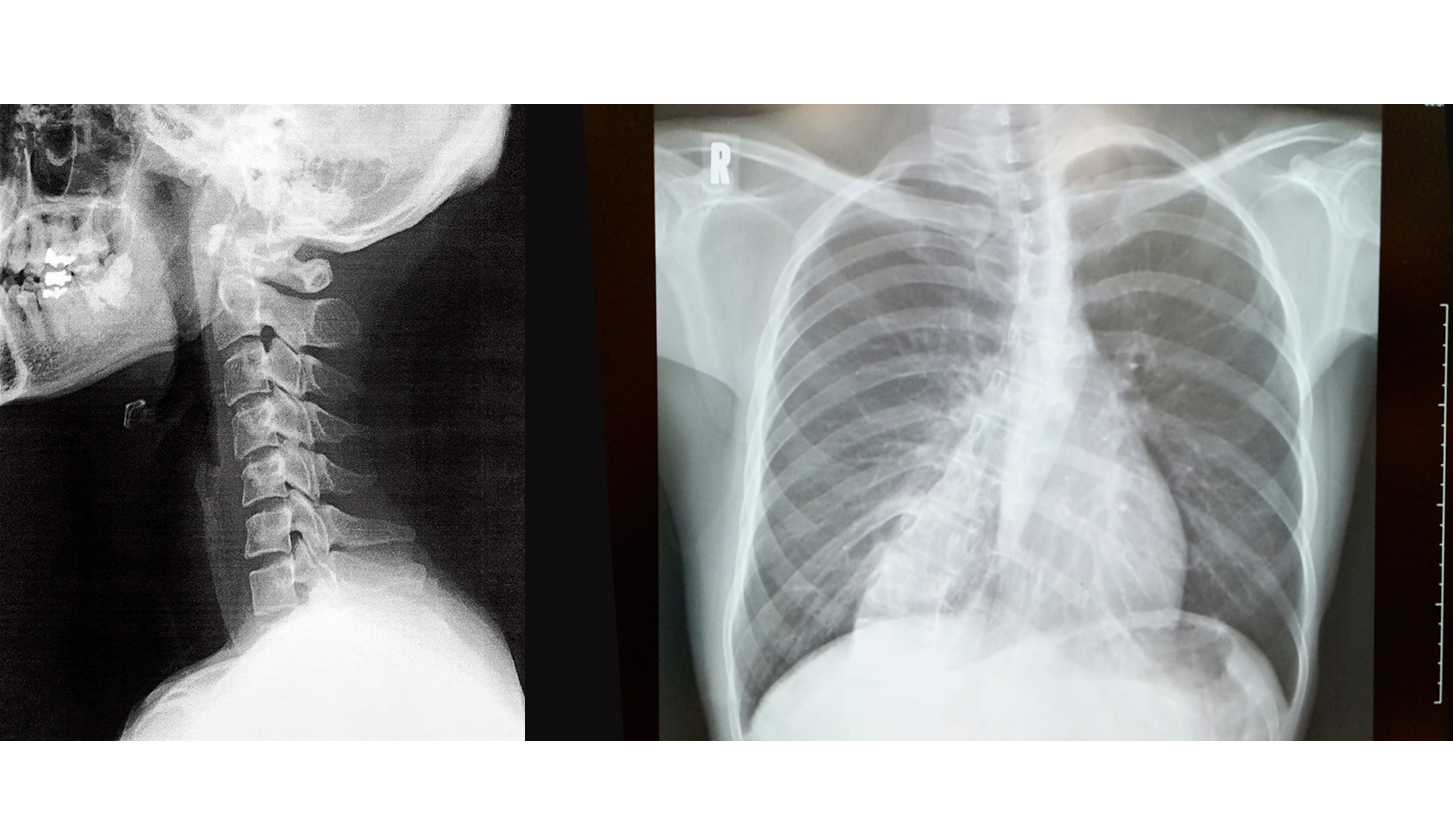

姿勢矯正は、子どもの成長の手助けだけでなく、姿勢の悪さがもたらす症状や、けがや病気によって変わってしまった姿勢を正す治療になります。

姿勢はその人の歴史を物語ると言われるほど、健康・老化・様々な病気と密接な関係があります。当院では不良姿勢の原因となる筋膜の癒着や硬化をリリース(除去)しながら、身体の柔軟性を高め、骨盤や背骨の歪みを治療していきます。

姿勢矯正には、まず、どこが悪いのか?患者様の訴えから、施術者が客観的に検査してその原因を探します。姿勢の悪い主な原因としては、猫背、円背、ストレートネック、交通事故の後遺症、手術後の後遺症、足の捻挫やぎっくり腰の庇いなど様々です。